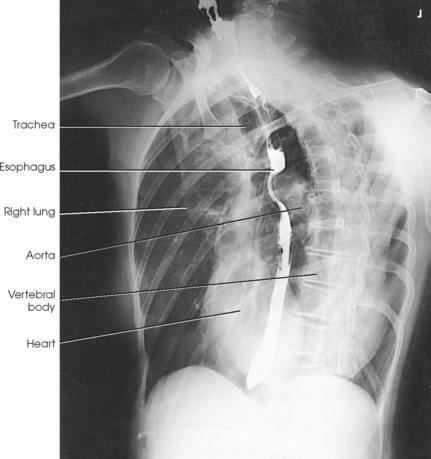

The esophagus lies just in front of the vertebral column, with its anterior surface in close relation to the trachea, aortic arch, and heart. This makes the esophagus valuable in certain heart examinations. When the esophagus is filled with barium sulfate, the posterior border of the heart and aorta are outlined well in lateral and oblique projections (Fig. 10-7). Frontal, oblique, and lateral images are often used in examinations of the esophagus. Radiography of the esophagus is discussed later in this chapter.

Fig. 10-7 A, PA projection of esophagus with barium sulfate coating its walls. B, PA oblique projection with barium-filled esophagus (RAO position).